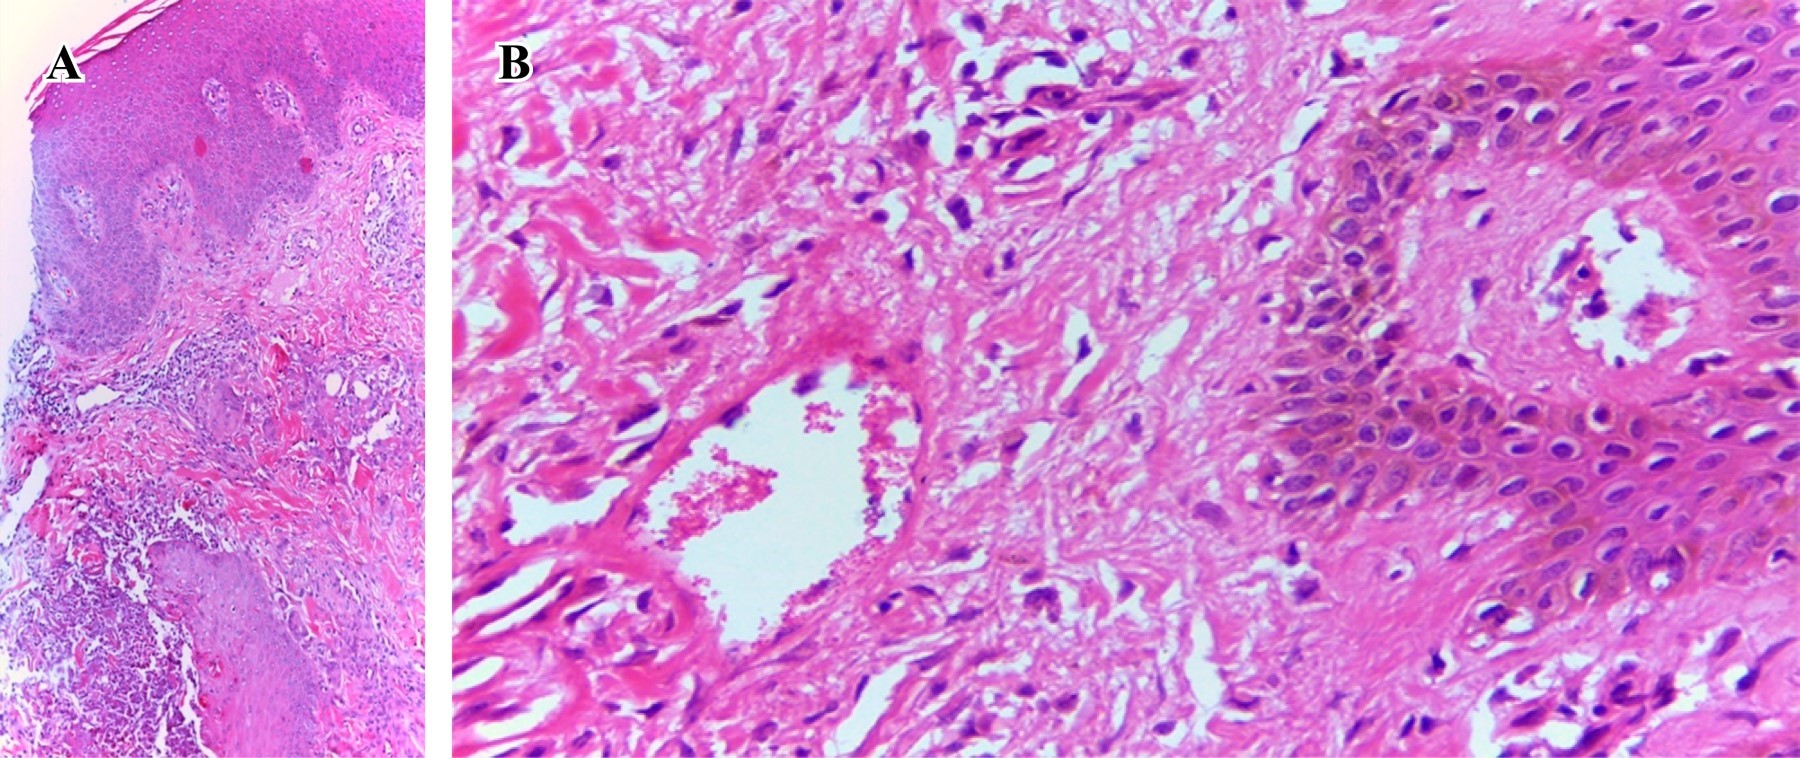

En todos los casos se realizaron biopsias de piel con técnica de sacabocado, encontrando infiltrados inflamatorios con respuesta a cuerpo extraño, así como elementos histomórficos compatibles con Histoplasma capsulatum (Figuras 4 y 5).

El diagnóstico puede ser realizado mediante el cultivo micológico, las pruebas moleculares, serologías y el estudio histopatológico;9,11 de éstos, el último representa la herramienta más accesible para la mayoría de escenarios y es considerada una prueba con suficiente sensibilidad y especificidad para establecer de manera contundente el diagnóstico. El estándar de oro continúa siendo el cultivo micológico con el uso de medios de cultivo convencionales para hongos, no obstante, el largo tiempo de incubación y la necesidad de espacios físicos adecuados para el manejo de esta clase de patógenos imposibilitan su uso de manera rutinaria. La detección de antígenos de Histoplasma capsulatum en fluidos corporales representa la prueba más rápida y sensible para el diagnóstico. Dentro de las pruebas moleculares la PCR y la NAAT representan herramientas prometedoras con sensibilidades reportadas de entre el 70 al 100%.9 Para el diagnóstico histopatológico se requiere de un alto índice de sospecha, los elementos histomórficos característicos son las células de entre 2 a 4 µm con gemación de base estrecha, en ocasiones rodeadas de un halo claro, que pueden encontrarse extracelulares, intracelulares, dentro de granulomas o inclusive intravasculares; para su identificación se utilizan tinciones como hematoxilina y eosina así como ácido peryódico de Schiff (PAS) y Gomori-Grocott. Se han descrito cuatro tipos histológicos basados en la reacción del hospedero contra el patógeno: tuberculoide, anérgica, mixta y secuelas.12